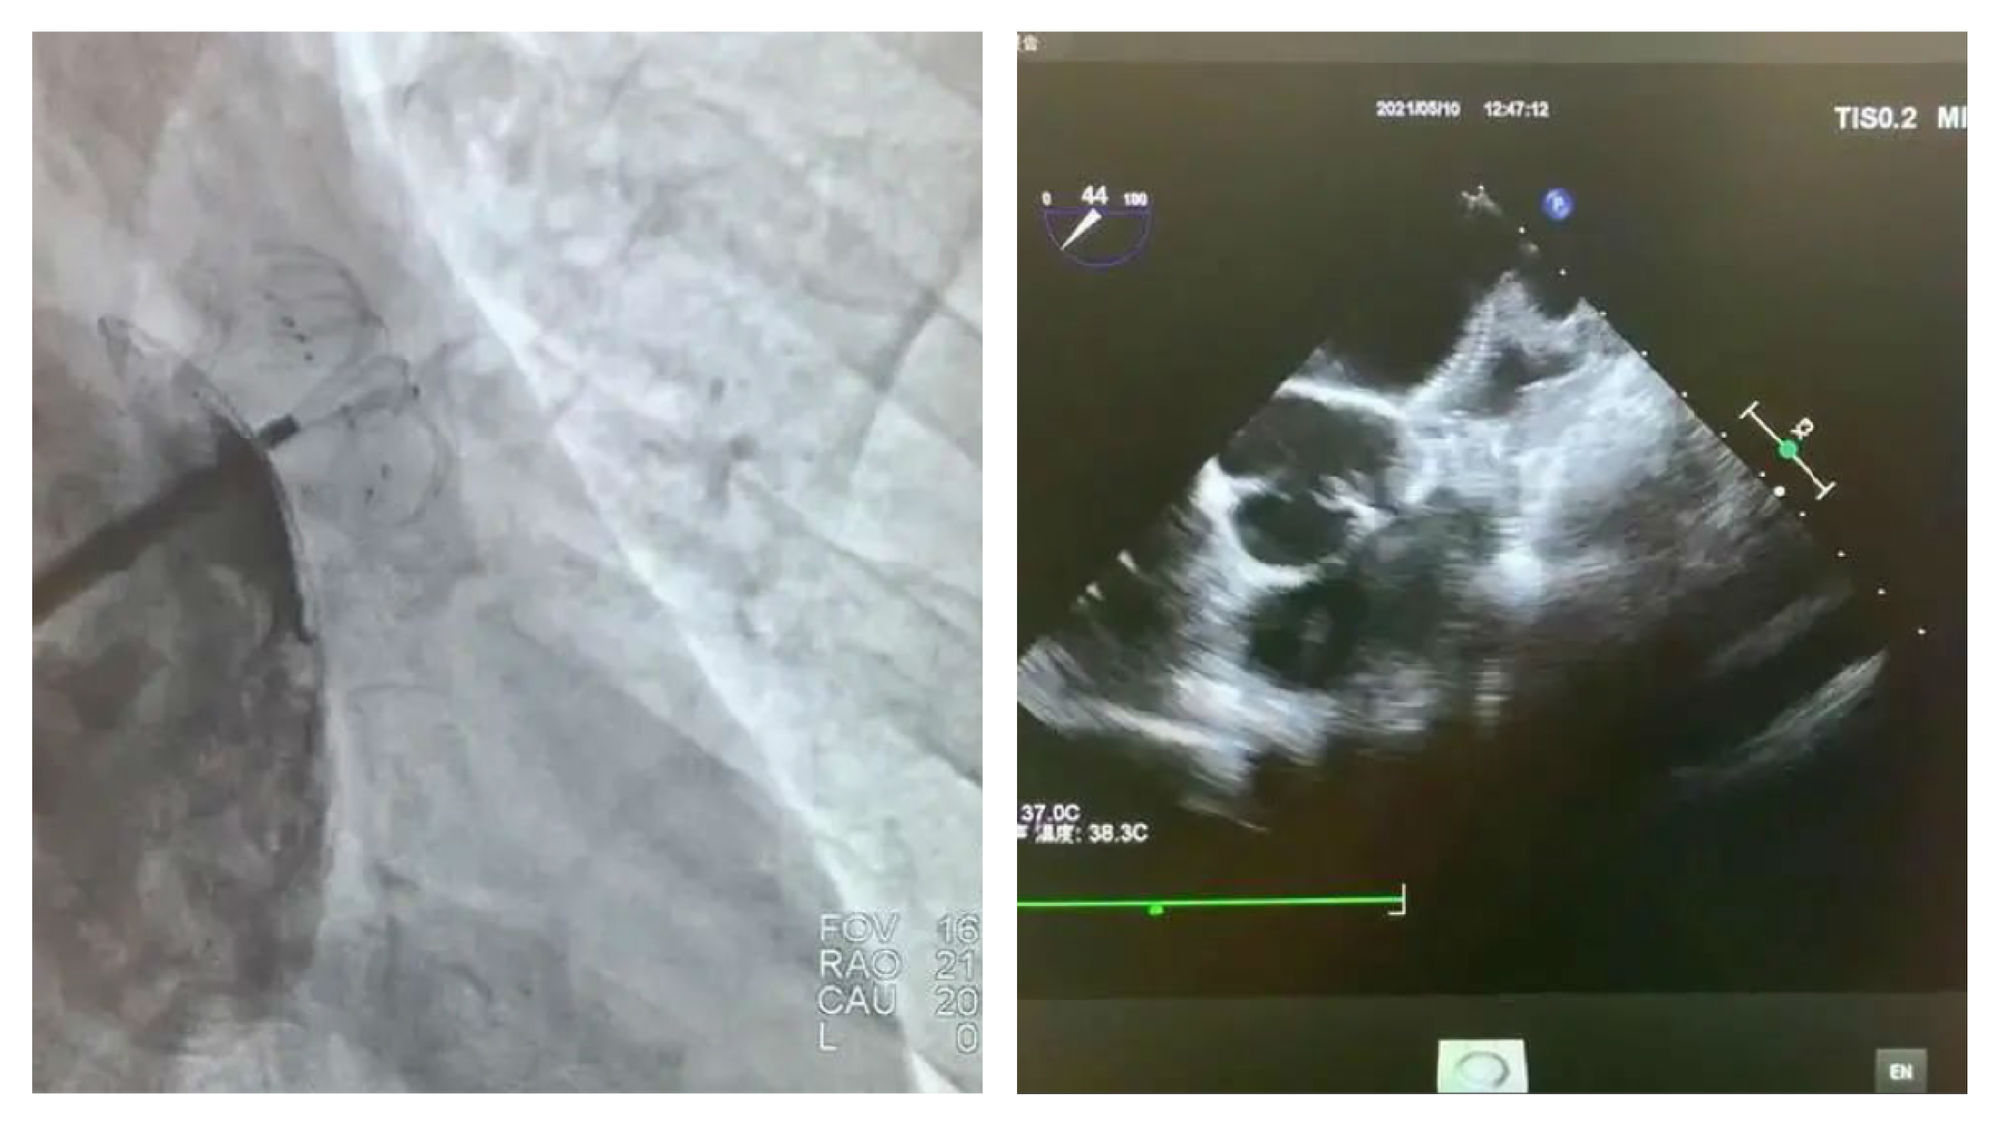

手术在局部麻醉下进行,术中造影显示患者为鸡翅型心耳,DSA下测量左心耳锚定区为22mm,封堵区为27mm。谭冠昶教授与卢谦教授决定选用型号为LT-LAA-2834的LAmbre™左心耳封堵器为患者进行手术封堵。

左心耳造影

锚定区及封堵区测量

DSA与超声显示封堵良好,无残余分流

术中LAmbre™左心耳封堵器牵拉稳定,食道超声下各角度显示封堵完美,符合COST原则。释放后,造影显示左心耳密封效果理想,无任何残余分流,且不影响周围组织结构,手术取得了令人满意的效果。